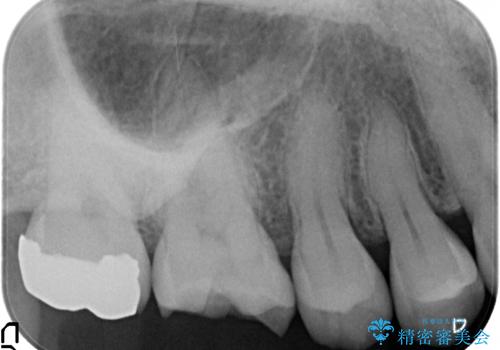

- 笑ったときに目立つ奥歯の銀歯を白くしたいという希望で来院されました。

銀歯を除去し、ジルコニアクラウンによる審美性の回復を計画します。